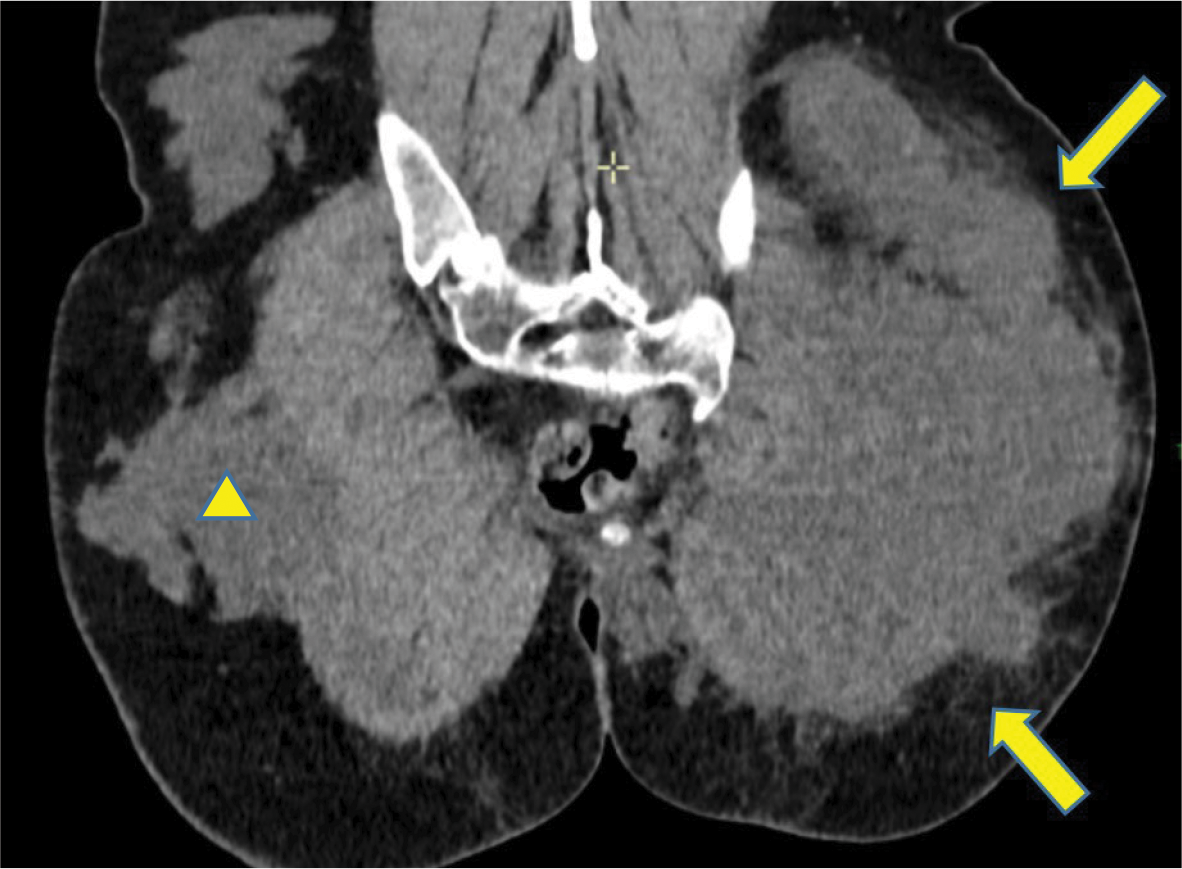

Figure 2

Diffuse infiltration of the subcutaneous fat surrounding the left gluteal fluid collection (

).